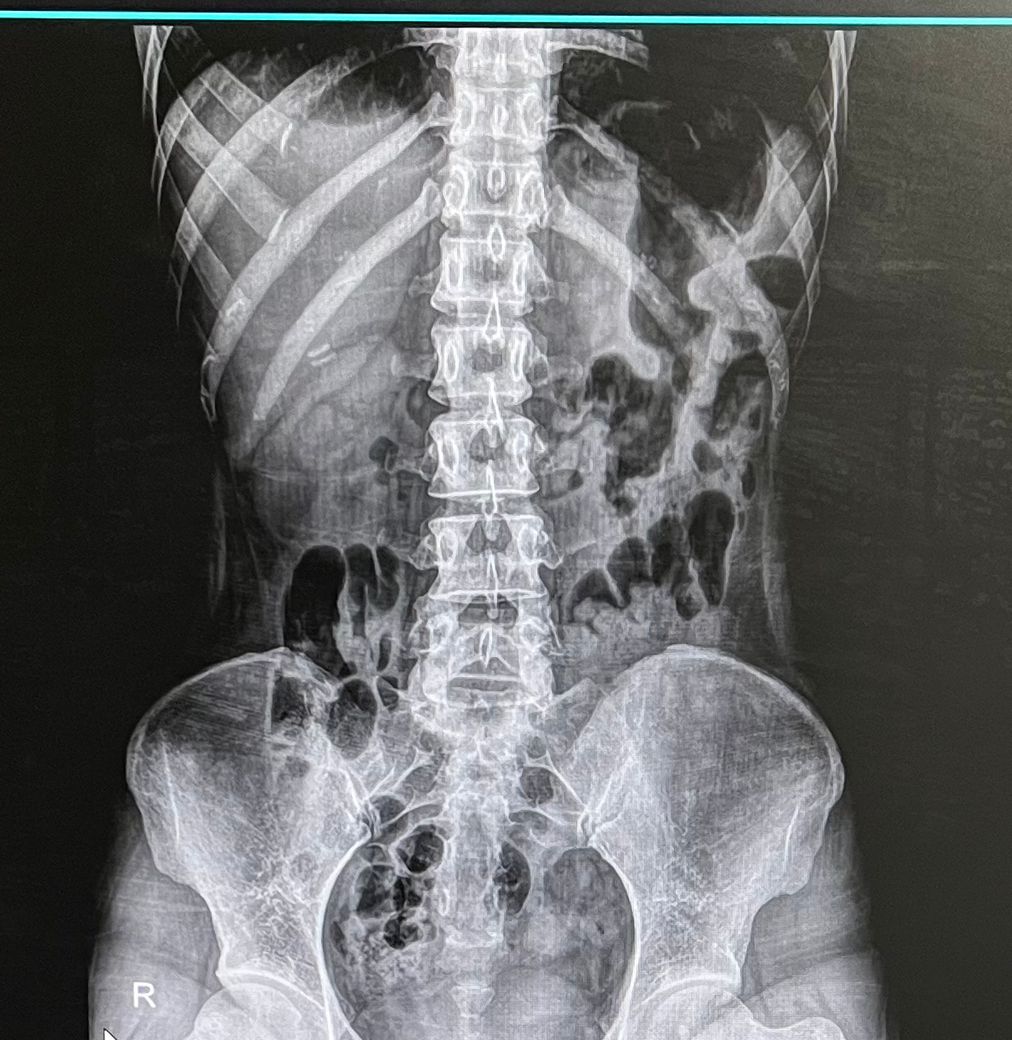

몇주전부터 방사통 재발해서 엑스레이 찍어봤더니

꼬리뼈에 가까운 5,6번? 뼈 간격이 3분의2정도 좁아졌습니다

최근 엑스레이 사진 첨부합니다

• 2번 째 사진